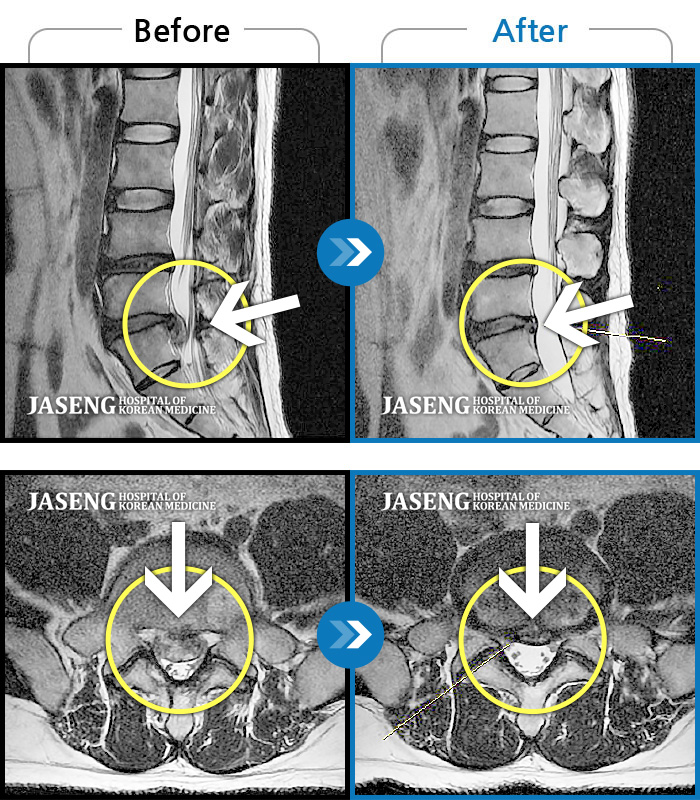

ȯںп Ǹ ǿ ԿǾ, ο ġ ۿ Ƿ ġḦ Ͻñ ٶϴ.